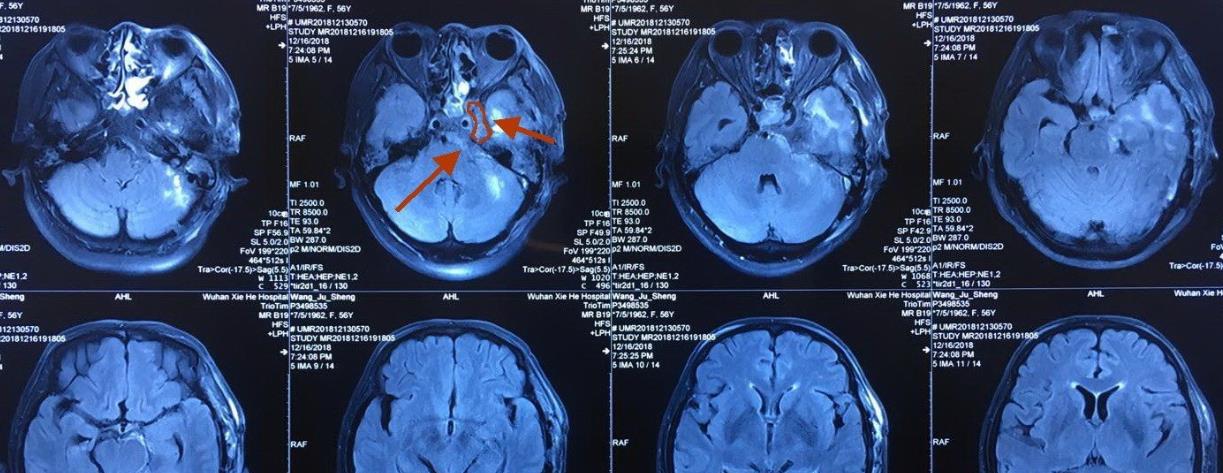

其次 , 磁共振成像的简称是MRI , 是医学影像学检查中的成像原理比较复杂的一种技术 , 它的基本原理是将人体置于特殊的磁场当中 , 用无线射频脉冲 , 激发人体内的氢质子 。

引起氢质子发生共振 , 并且吸收能量 , 在停止射频脉冲后 , 氢质子在特殊的频率 , 发出微弱的电磁信号 , 探测器可以捕捉到这种微弱的电磁信号 , 并且通过电子计算机的处理转换得到人体内部的组织和器官的图像 。

核磁共振检测主要是通过高能电子计算机进行采集方式来产生磁共振动的信号再通过数字重建技术的方式转换成图像 。

但是核磁共振同时还有检查的禁忌症 , 比如有心脏起搏器的患者禁止检查 , 因为核磁共振可以多方位、多序列成像 , 对软组织分辨率极高 , 但对显示钙化和气体性的病变比较差 。